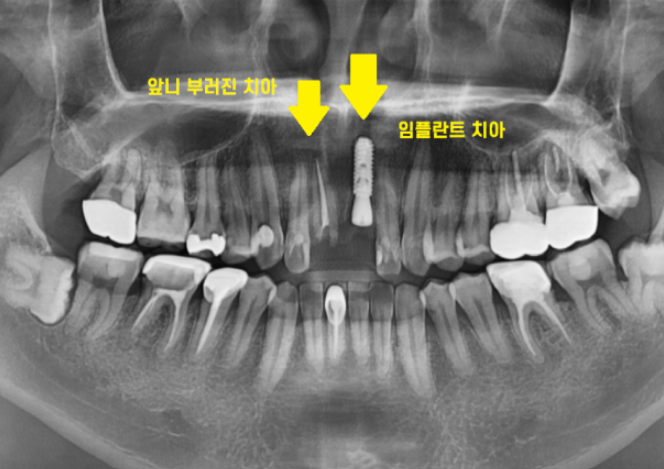

이런 이런

치료 받는 옆에 치아가 똑.. 부러져버렸네요

치아 1개가 또 부러졌네요.

잇몸 뼈 안쪽으로 뿌리만 남아있는 상황입니다.

남아있는 치아가 충치도 있고

부러진 양도 많고

상태가 영… 안좋네요ㅠㅠ

결국 옆에 치아도 발치를 진행했습니다.

발치 후 임플란트를 하였는데요.

임플란트 치료 후 사진입니다.

변수가 발생하여

당초 계획된 것보다 치료기간이 길어지긴 하였지만

잘 마무리가 되었습니다.